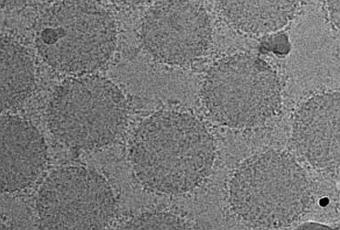

En pratique, ces chercheurs tirent parti d'un phénomène unique propre aux nanoparticules : les biomolécules présentes dans le sang de sujets en bonne santé ou atteints de maladies, forment différents profils de couronne (voir visuel ci-dessus) autour des nanoparticules. En d’autres termes, les nanoparticules recueillent un revêtement unique et spécifique de ces protéines présentes dans le sang. Les chercheurs apportent la preuve que ces couronnes forment des modèles différents et bien spécifiques chez les personnes atteintes de cancer.

Pour tester les échantillons de sang à la recherche de signatures de maladie précoces, l'équipe a mis au point un réseau de capteurs composé de 3 liposomes différents à réactivité croisée, des molécules grasses qui induisent la formation de couronnes protéiques. L'équipe a ensuite testé des échantillons provenant de 5 patients, présentant chacun un type de cancer différent : cancer du poumon, glioblastome, méningiome, myélome et cancer du pancréas. L’équipe constate alors que chaque cancer est associé à un modèle de couronne protéinique spécifique, détectées par le réseau de capteurs à nanoparticules, fournissait une « empreinte digitale » unique pour chaque type de cancer (visuel ci-contre). L’équipe a ensuite retesté l’outil sur des échantillons de sang provenant de 15 personnes qui environ 8 années plus tard ont reçu un diagnostic de cancer.